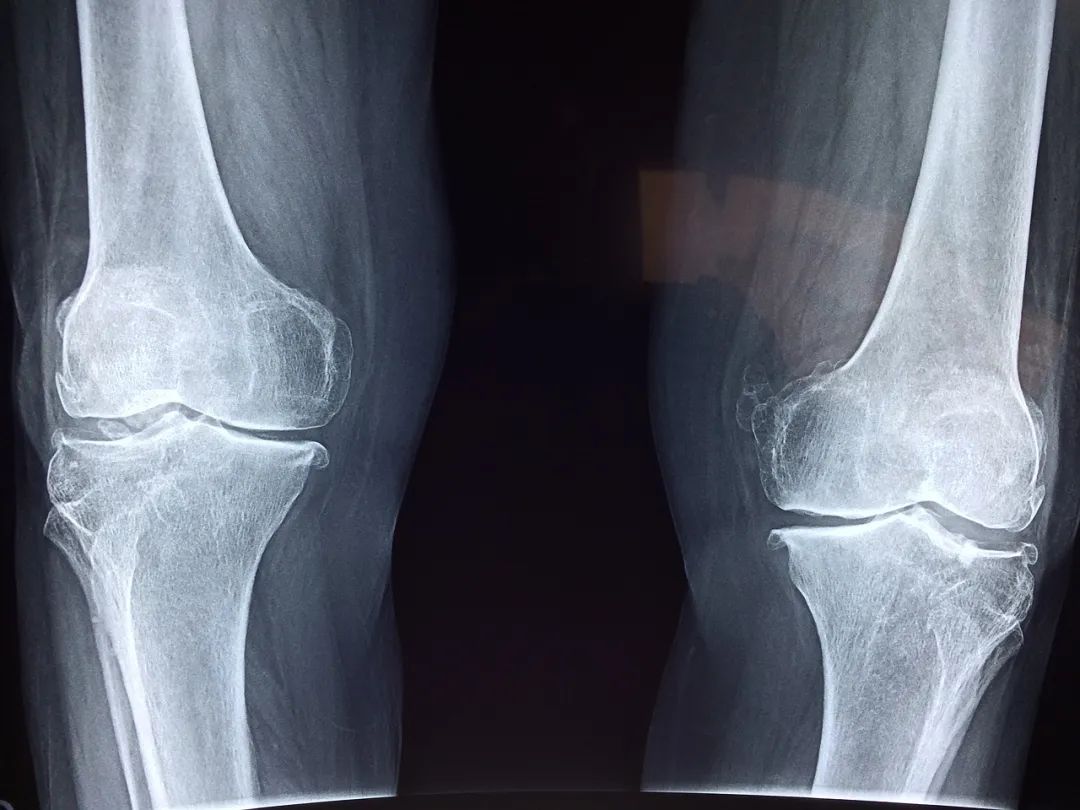

膝关节出现这些症状,可能已经提示关节受损

那么我们膝关节常出现的问题大概有两类:

疼

这是最常见的情况,突然觉得膝盖开始疼了,疼痛有由轻到重的区别,再一个就是它的部位,如果用手掌去摸到自己左侧的膝盖的话,用手掌心去扣住膝盖上面的髌骨,扣住它之后,当大拇指自然下垂的时候,能够碰到一个间隙,这个是膝关节内侧的间隙,如果这个位置疼痛,要小心半月板或者骨关节炎的一些问题,如果这个位置更靠上方或者更靠膝关节的下方,那有可能是来自于韧带,这是我们根据疼痛的部位来判断的。

2

响声

有的时候膝关节会出现一些响声,很清脆的一次弹响,不伴有疼痛的,可能是一些生理性的弹响,比如说我们滑膜增生等。如果退行性的骨关节病、关节炎,它的响声是非常有特征性的,就像冬天你去握一把雪,雪球就发出咯吱咯吱的声音,这种握雪感是非常典型的骨关节炎的一个表现,叫作骨摩擦音。